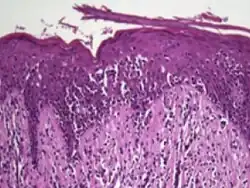

Histology

The criteria for the disease are established on the skin biopsy by the presence of the following:[18]

- Presence of cancer cells with twisted contours (cerebriform nuclei)

- In the patch and plaque stages, the cancer cells are seen in the epidermis (the most superficial layer of skin).[19] This is referred to as epidermotropism.

- Pautrier's microabcesses, aggregates of four or more atypical lymphocytes arranged in the epidermis. Pautrier microabcesses are characteristic of mycosis fungoides but are generally absent.

- In the tumour stage, the cancer cells move into the dermis (the deeper layer of skin)[19]

- Large cell transformation, where clonally identical lymphocytes in the lesion exhibit hypertrophy. In transformed cells, presence of the CD30 receptor is associated with improved survival[20]

In the mycotic stage, infiltrative plaques appear and biopsy shows a polymorphous inflammatory infiltrate in the dermis that contains small numbers of frankly atypical lymphoid cells. These cells may line up individually along the epidermal basal layer. The latter finding if unaccompanied by spongiosis is highly suggestive of mycosis fungoides. At this stage, biopsies can reveal medium to large lymphocytes with convoluted, cerebriform nuclei in the epidermis, which are larger than the lymphocytes typically seen in inflammatory dermatoses. These atypical lymphocytes are mature skin-homing CD4+ T cells, and their presence in the epidermis is a key feature of early MF. Additionally, the cells may form microabscesses in the epidermis, known as Pautrier’s microabscesses.[16] In the tumorous stage a dense infiltrate of medium-sized lymphocytes with cerebriform nuclei expands the dermis.